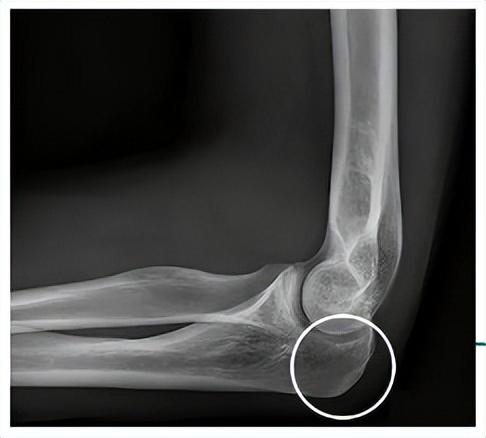

01-手肘

我們進行肘擊時

受力的部位是一塊

叫做“尺骨鷹嘴”的骨骼結構

這個骨頭又尖又硬

還沒有肌肉、脂肪的包裹

它發出的擊打力量

能夠最大程度的傳導出來